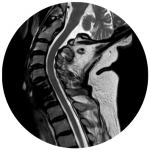

Halswirbelsäule / Brustwirbelsäule

Mikrochirurgische ventrale Versorgung von Bandscheibenvorfällen, Spinalkanalstenosen, Myelopathien, Neuroforamenstenosen mittels Bandscheibenprothese/ Cages/ Wirbelkörperersatz und ggf. Schrauben und Plattenabstützung